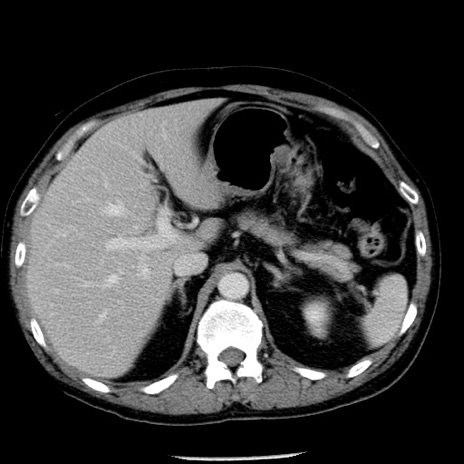

症例29(横断像)

【症例】40歳代男性

【現病歴】2日前から胃痛あり。徐々に周期的な激痛に変化した。本日になっても激痛があるため受診。

【身体所見】意識清明、BT 38-39℃台あり、腹部:膨満、やや硬、右下腹部に圧痛あり。

【データ】WBC 8500、CRP 23.26